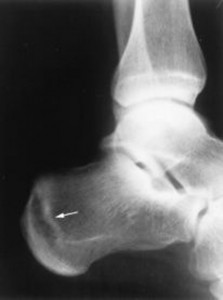

Συμπτώματα κατάγματος στην πτέρνα

Τα κατάγματα της πτέρνας είναισ πάνια. Οι ασθενείς που παρουσιάζονται με κάταγμα της πτέρνας, οι οποίοι είναι συνήθως αθλητές, στρατιώτες και μπαλαρίνες, παραπονιούνται για πόνο στο εσωτερικό και εξωτερικό μέρος της πτέρνας, ο οποίος αυξάνεται σημαντικά κατά την άθληση και πολύ συχνά καθιστά το περπάτημα αδύνατο. Ακόμα υπάρχει αυξημένος πόνος κατά την νύχτα.